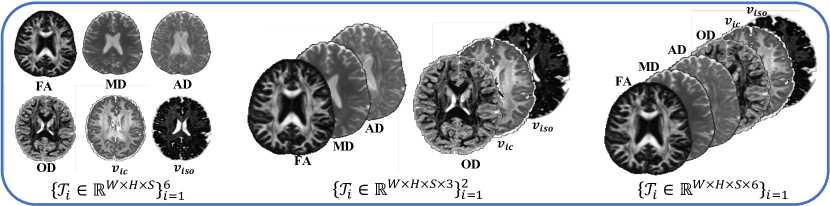

Leveraging multiple microstructural features from different diffusion models contributes to a more comprehensive understanding of brain microstructure. As presented in Figure 1, multiple microstructural parameters from different diffusion models rely on the same biological tissue, sharing the same anatomical and diffusion information, thus demonstrating high correlation. However, despite the promising achievements, the efficiency and accuracy of multi-parametric estimations remain limited as previous deep learning-based studies have primarily focused on estimating multi-parametric maps individually using isolated signal modeling. Although some research has employed multi-parametric learning [25, 33, 34, 35], they tend to directly output multiple parameters without considering the correlation among parameters.

5.2 Discussion on the dimensions of the multi-parameter Tensor

The high dimensionality of multiple parameters allows for various methods to decompose this tensor. This section explores the impact of tensor dimensions on the proposed method. We conducted a detailed study on three tensor dimensions presented in Fig. 6: decomposing the six parameters as individual tensors, grouping the DTI and NODDI parameters into two sets, and merging all six parameters for decomposition. The findings in Fig. 7 suggest that, when considering 18 DWIs (with uniform 6 diffusion directions per shell at b-values of 1000, 2000, and 3000 ), the best performance is achieved when merging the six parameters, highlighting the effectiveness of the DeepMpMRI in leveraging the correlations between multiple parameters and the redundancy of high-dimensional data.